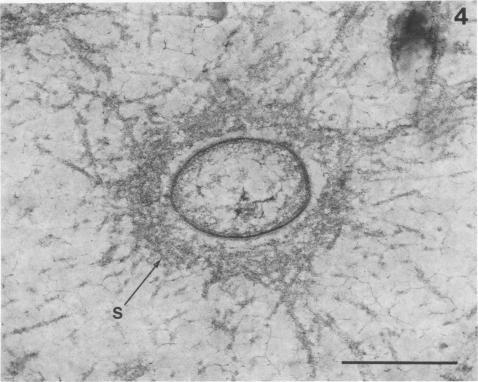

Direct electron microscopic examination of postmortem lung material from cystic fibrosis patients infected with Pseudomonas aeruginosa has shown that these bacterial cells form distinct fiber-enclosed microcolonies in the infected alveoli. Similar examination of bronchoscopy material from infected cystic fibrosis patients showed that the fibres of the enveloping matrix are definitely associated with the bacterial cells. The fibers of the extracellular matrix stain with ruthenium red and are therefore presumed to be polyanionic. When mucoid strains of P. aeruginosa were recovered from cystic fibrosis patients and grown in a suitable liquid medium, they were found to produce large microcolonies whose component cells were embedded in a very extensive matrix of polyanionic fibers that could be stabilized by reaction with antibodies to prevent collapse during the dehydration steps of preparation for electron microscopy. When these mucoid strains of P. aeruginosa were used to produce pulmonary infections of rats by the agar bead method, the infected alveoli contained large fiber-enclosed bacterial microcolonies. We conclude that the cells of P. aeruginosa that infect cystic fibrosis patients form microcolonies that are enveloped in a fibrous anionic matrix and that these microcolonies can be duplicated in in vitro cultures and in animal model systems.